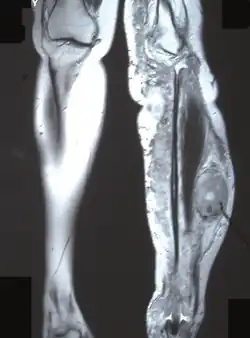

- powikłania ortopedyczne: dysplazje i deformacje kostne, zwłaszcza skolioza odcinka piersiowego kręgosłupa, dysplazja skrzydeł większych kości klinowej, deformacje kości strzałkowej i piszczelowej, złamania patologiczne z tendencją do tworzenia stawów rzekomych (25%)